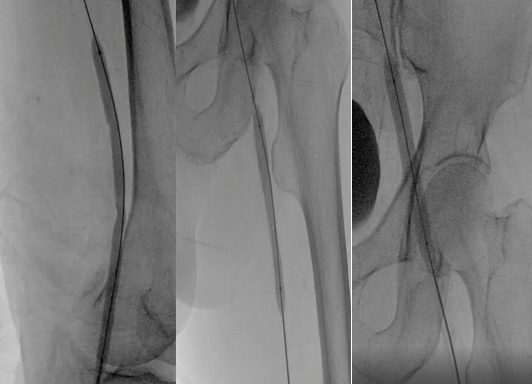

彩超引导下穿刺左侧腘静脉行造影示:左侧髂股静脉管腔闭塞,大量侧支循环建立。

利用超滑导丝及微导丝反复尝试通过髂股静脉闭塞段引入球囊扩张导管行髂股静脉球囊扩张成形,扩张过程中可见明显切迹。